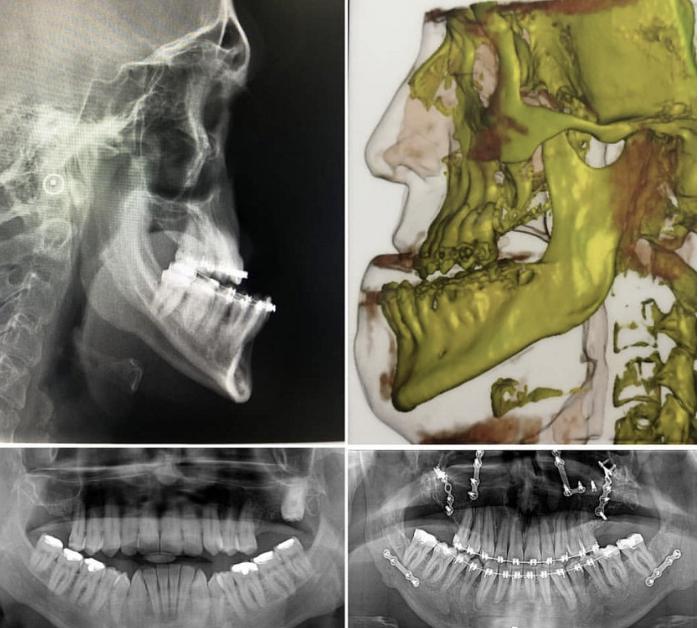

由于成人患者骨骼没有生长潜力,只有骨改建能力,当牙齿需要较大范围移动时,骨皮质并不能跟随牙齿移动,不利于齿槽骨的健康,所以成人患者牙齿移动范围有很大局限性。为了提高正畸治疗效果,扩大正畸适应症,通过切开、断开牙根部的骨皮质(骨松质是连接的),当牙齿移动时,骨皮质与牙齿同时移动,减小了骨的阻力,牙齿移动的范围更大、速度更快。所以骨皮质切开术不但能解决中度骨性龅牙,还可以实现“快速正畸”。

为了使骨皮质切开效果更加完美,在骨皮质切开同时在表面植骨(盖氏Bio-Oss骨粉),可以更大范围、更快地移动牙齿,同时能够更好的保护牙槽骨健康,因为通过植骨,使骨皮质加厚加高,比术前更加坚固。

所以针对轻度和中度的骨性龅牙,骨皮质切开术联合正畸治疗一定会比单纯正畸治疗效果更好、更快。